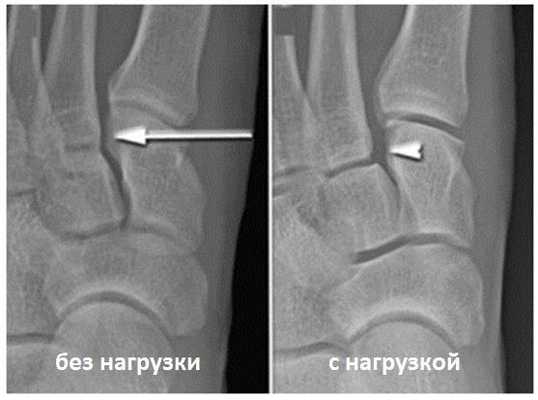

Для инструментальной диагностики используются рентгенограммы с\без нагрузки в сравнении со здоровой стороной, при их малой информативности рекомендовано выполнение стресс-рентгенограмм, аналогично приведёному выше тесту на нестабильность.

При рентгенографии все снимки выполняются в сравнении со здоровой стопой. Существует несколько основных рентгенологических признаков повреждения сустава Лисфранка. 1. Отсутствие параллельности медиального края основания 2-й плюсневой и медиального края медиальной клиновидной кости 2. Расширение между основаниями 1 и 2 плюсневых костей 3. Наличие костного фрагмента в области основания 2-1 плюсневой кости 4. Тыльный подвывих на боковой проекции 5. Разрыв линии предплюсне-плюсневого сочленения.

Отдельно стоит разобрать тему разрыва связки Лисфранка с изолированной нестабильностью 2 предплюсне-плюсневого сустава. Частота данного повреждения значительно выросла за последние 50 лет в связи с популяризацией спорта. Также крайне высота частота отсроченной постановки диагноза. При этой патологии пациента беспокоит боль по тыльной поверхности 1-2-3 предплюсне-плюсневых суставов при физической нагрузке. Часто при осмотре удаётся обнаружить деформацию в данной области. Если осмотр производится отсрочено через несколько недель или месяцев после травмы то клинически определить нестабильность уже не удастся, однако на рентгенограммах с нагрузкой будет виден диастаз между медиальной клиновидной костью и основанием 2 плюсневой кости.